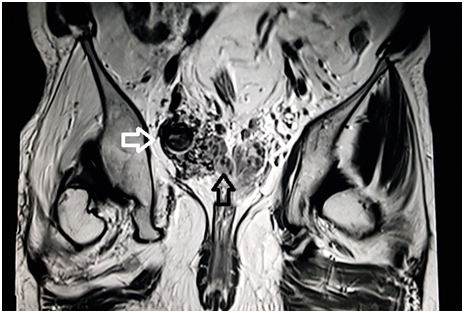

A 39 year old male presented with the chief complaint of pelvic discomfort and on and off haematuria. It was not associated with fever or urinary retention. No bowel symptoms were noted. Patient had history of paralytic poliomyelitis in his childhood and walked with crutches. On laboratory examination, patient was found to have deranged renal function tests with elevated creatinine level. Hence, we conducted MRI pelvis with MR urography to look for the urinary systemand to look for the status of the the pelvic muscles and joints. MR study showed multiple tortuous dilated vessels on the right side of pelvis suggestive of pelvic arteriovenous malformation (Figure 1&2). The arterial supply was noted from multiple branches of the right internal iliac artery and venous drainage was noted into right external iliac vein and deep external pudendal vein. The tangle of vessels was abutting the right lateral wall of urinary bladder, prostate and right seminal vesicle medially (Figure 1&3). It was abutting the obturatorinternus muscle laterally. There wasasymmetric thickening of the right lateral wall of urinary bladder adjacent to the vascular malformation (Figure 1). It was not associated with perivesicular fat strandings or enlarged locoregional lymphnodes. No restriction of diffusion was noted in DWI images. Prostate and bilateral bilateral seminal vesicles were normal in signal intensity and morphology. As a sequalae of childhood poliomyelitis, diffuse atrophy of pelvic muscles was noted that was more prominent on the right side (Figure 4&5). T1 and T2 high signal intensity suggestive of fatty replacement was noted in bilateral psoas and right obturaterinternus mucle. Fatty atrophy of bilateral hip and proximal thigh muscles were also seen (Figure 5). Abduction and external rotation was noted at bilateral hip joints (Figure 4). Histological examination of the bladder wall revealed polypoid bladder mucosa with chronic inflammation consistent with polypoid cystitis. Arteriovenous malformation was managed with intra-arterial coil embolization and subsequently the patient’s symptoms improved.

Figure 2 MRI coronal T2 weighted image through the pelvis demonstrate dilated tortuous vessels (white arrow) on the right side of pelvis abutting the right seminal vesicle (black arrow).